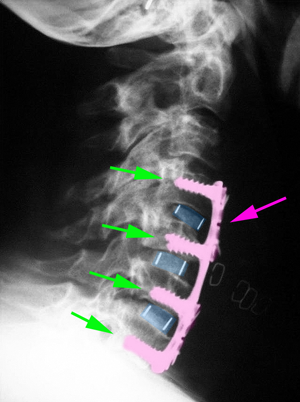

• Η Πρόσθια Αυχενική Σπονδυλοδεσία